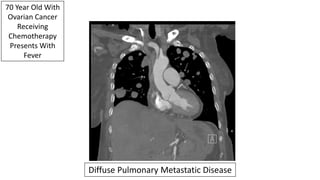

70 Year Old With

Ovarian Cancer

Receiving

Chemotherapy

Presents With

Fever

Diffuse Pulmonary Metastatic Disease